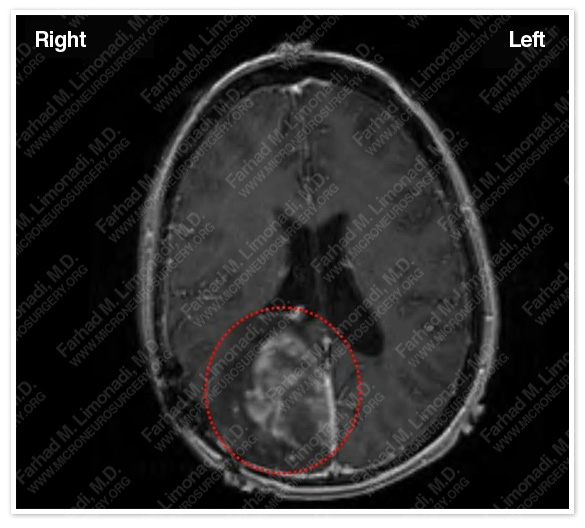

- 32-year-old lady with known diagnosis of oligodendroglioma in right occipitoparietal region and three previous subtotal resections of this tumor who was presented to us for complete resection.

The tumor is outlined in a red dotted circle.